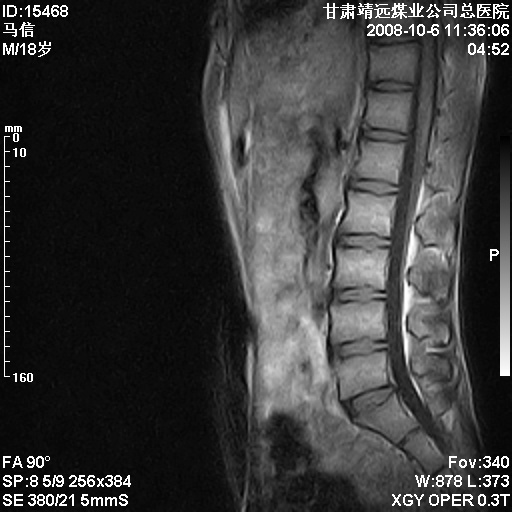

患者18岁,学生,在玩耍中受伤来检查,患者喜欢打篮球。颈椎内异常信号影,我们考虑占位,但是不像占位,又考虑硬膜囊的增厚,大家关建看颈椎椎管内的那个异常占位信号

腰椎的改变是不是正常发育的改变,还是打篮球的长期慢性损伤。

考虑 c3-4 c4-5 c5-6椎间盘突出,l3-4 l4-5 l5-s1椎间盘变性

颈椎建议做增强扫描;腰椎诸椎终板骨骺炎。

后纵韧带增厚,颈2/3、3/4、4/5、5/6椎间盘变性、突出;椎体有旋转,提示椎小关节有问题;腰椎间盘变性,许莫氏结节。

后纵韧带增厚,颈2/3、3/4、4/5、5/6椎间盘变性、突出;椎体有旋转,提示椎小关节有问题。腰椎诸椎体终板骨骺炎可能性大!支持!